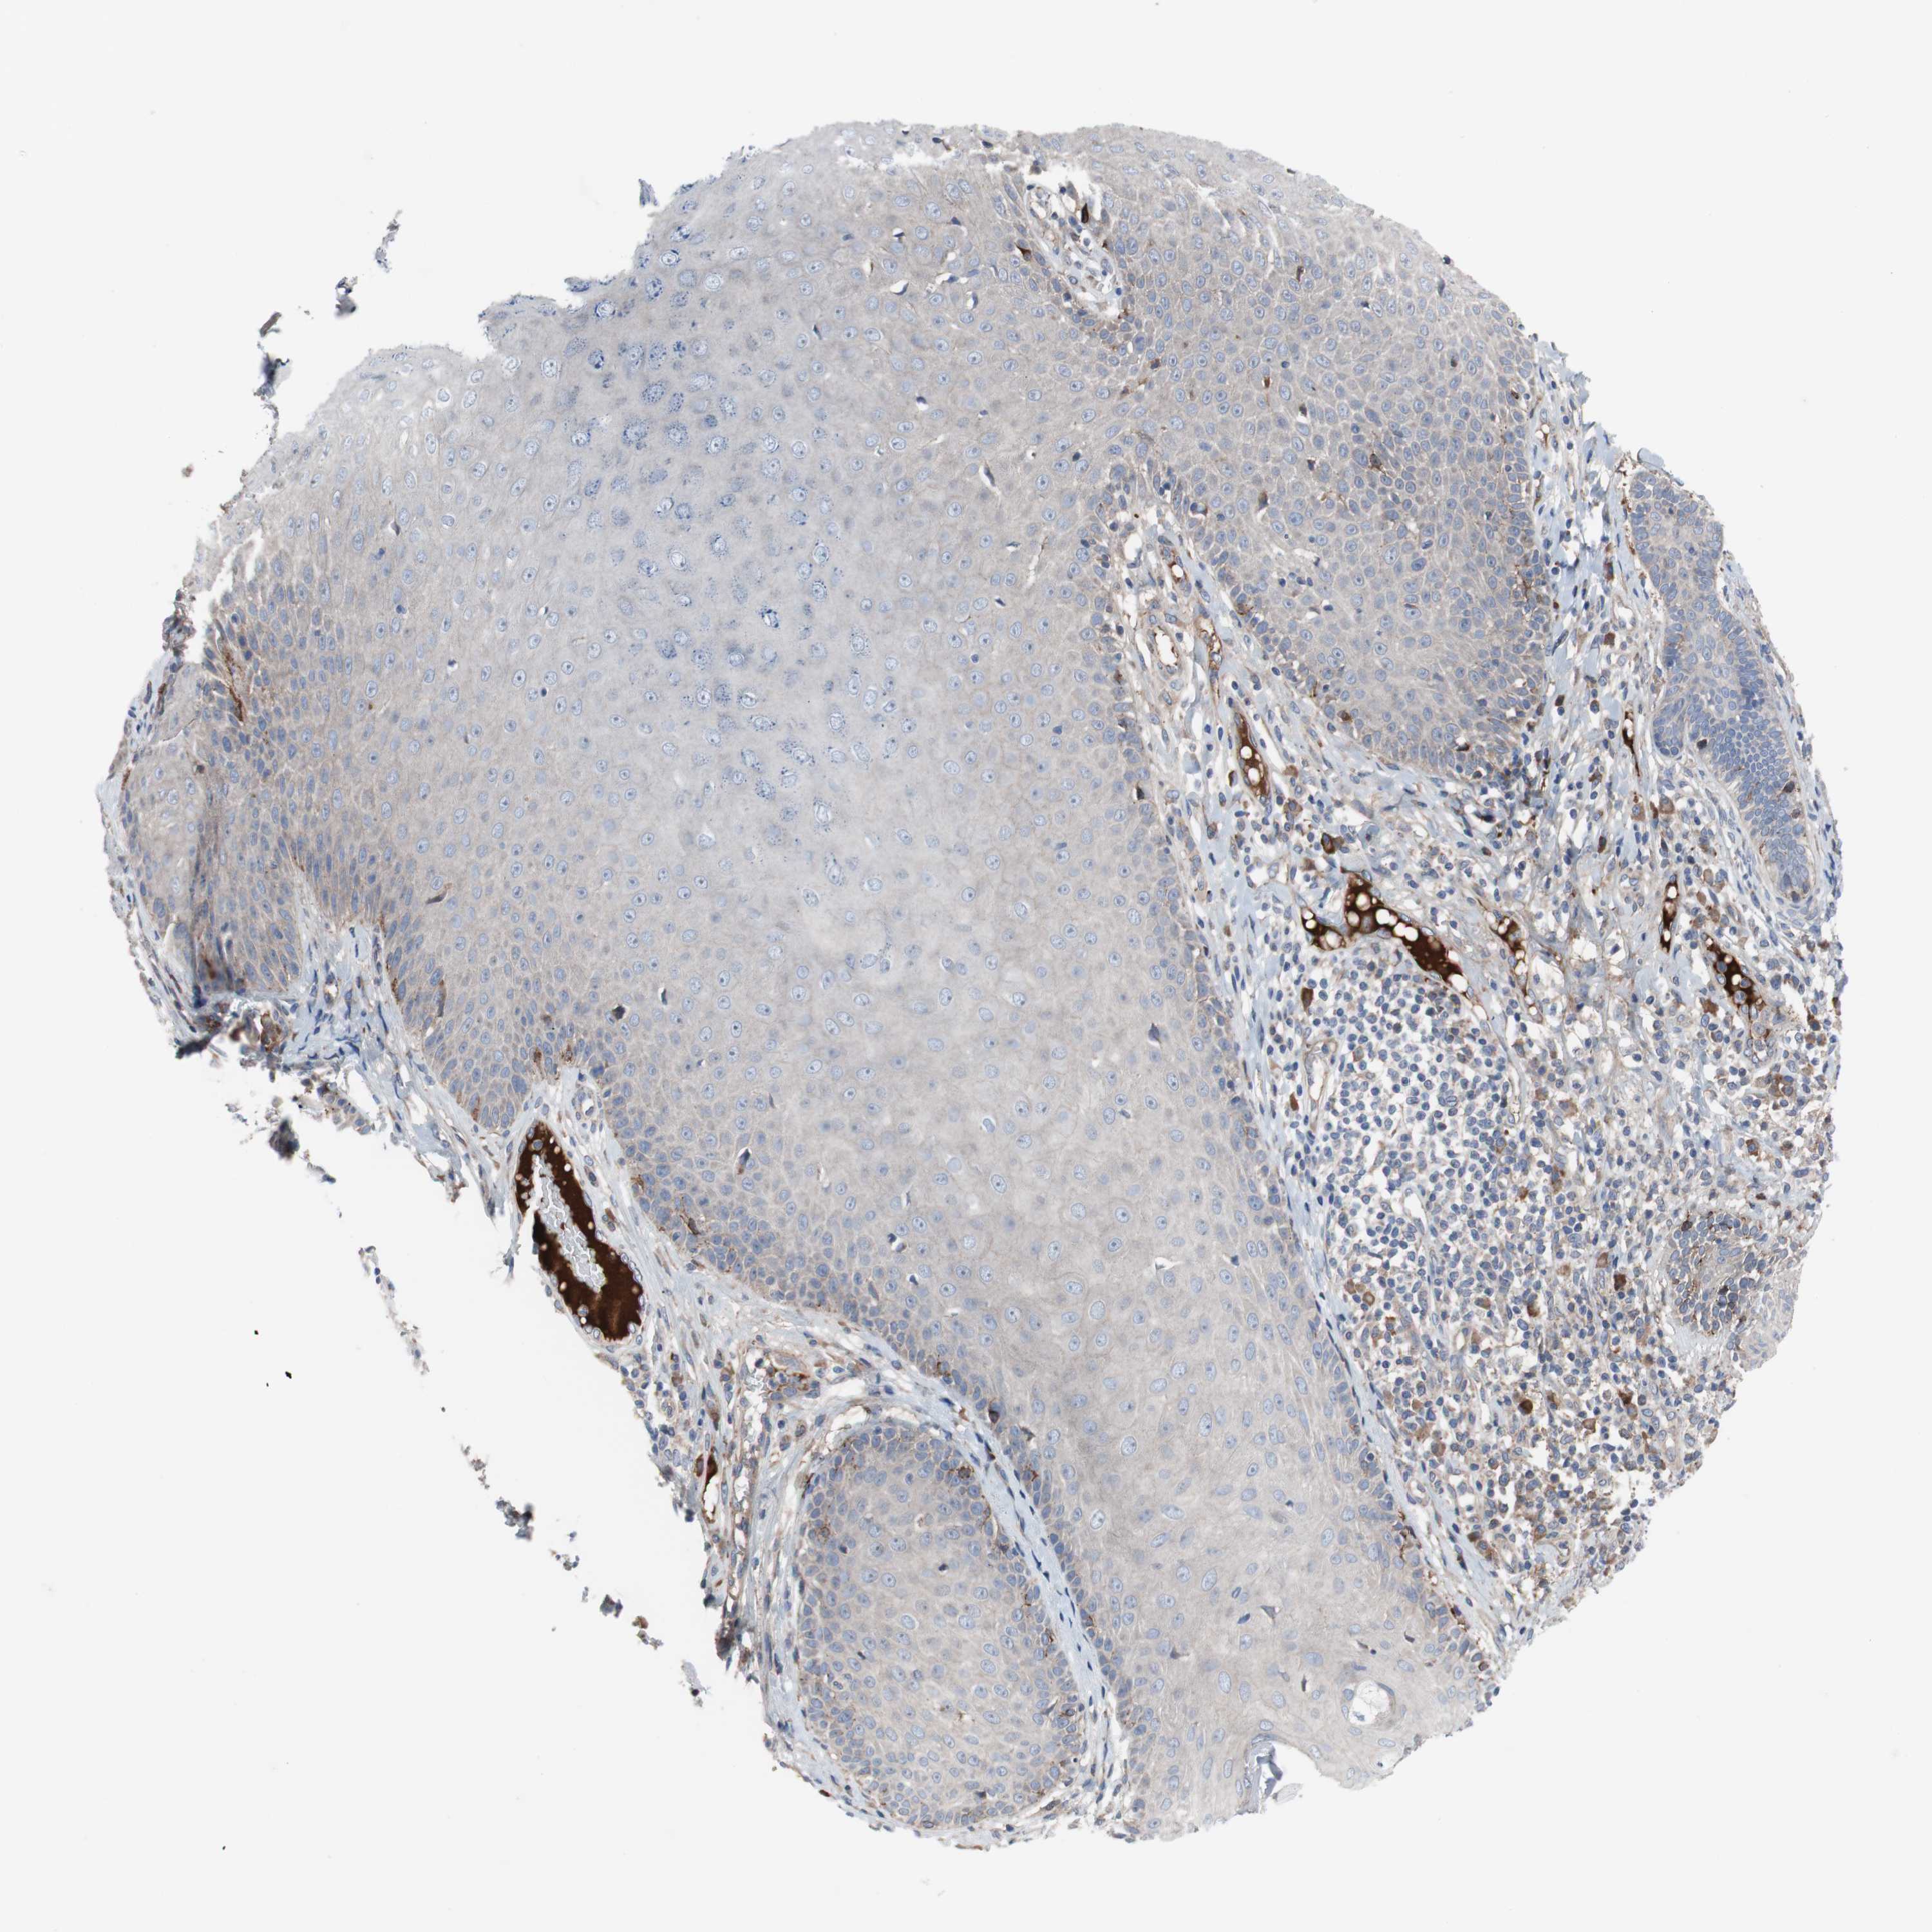

SKIN CANCER - Protein expressioni

A mouse-over function shows sample information and annotation data. Click on an image to view it in a full screen mode. Samples can be filtered based on level of antibody staining by selecting one or several of the following categories: high, medium, low and not detected. The assay and annotation is described here.

Each image is clickable and will lead to virtual microscopy that enables deeper exploration of all samples and also displays staining intensity scores, fraction scores and subcellular localization as well as patient and tissue information for each sample.

Antibody HPA006874

Antibody HPA007208

Staining

High

Medium

Low

Not detected

Intensity

Strong

Moderate

Weak

Negative

Quantity

>75%

75%-25%

<25%

None

Location

Nuclear

Cytoplasmic/membranous

Cytoplasmic/membranous,nuclear

Squamous cell carcinoma, NOS

Basal cell carcinoma